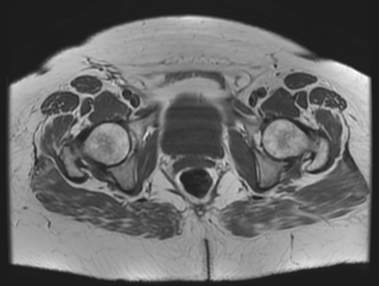

Standardized body region labelling of individual images provides data that can improve human and computer use of medical images. A CNN-based classifier was developed to identify body regions in CT and MRI. 17 CT (18 MRI) body regions covering the entire human body were defined for the classification task. Three retrospective databases were built for the AI model training, validation, and testing, with a balanced distribution of studies per body region. The test databases originated from a different healthcare network. Accuracy, recall and precision of the classifier was evaluated for patient age, patient gender, institution, scanner manufacturer, contrast, slice thickness, MRI sequence, and CT kernel. The data included a retrospective cohort of 2,934 anonymized CT cases (training: 1,804 studies, validation: 602 studies, test: 528 studies) and 3,185 anonymized MRI cases (training: 1,911 studies, validation: 636 studies, test: 638 studies). 27 institutions from primary care hospitals, community hospitals and imaging centers contributed to the test datasets. The data included cases of all genders in equal proportions and subjects aged from a few months old to +90 years old. An image-level prediction accuracy of 91.9% (90.2 - 92.1) for CT, and 94.2% (92.0 - 95.6) for MRI was achieved. The classification results were robust across all body regions and confounding factors. Due to limited data, performance results for subjects under 10 years-old could not be reliably evaluated. We show that deep learning models can classify CT and MRI images by body region including lower and upper extremities with high accuracy.